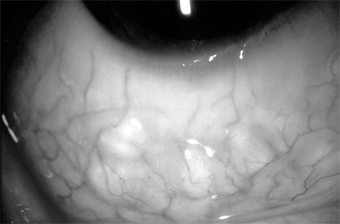

This is a group of conjunctival diseases, usually unilateral, characterized by low-grade fever, grossly visible preauricular adenopathy, and one or more conjunctival granulomas (Figure 5-25). The commonest cause is cat-scratch disease, but there are many other causes, including Mycobacterium tuberculosis, Treponema pallidum, Francisella tularensis, Pasteurella (Yersinia) pseudotuberculosis, Chlamydia trachomatis serotypes L1, L2, and L3, and Coccidioides immitis.

Figure 5-25

Figure 5-25: Conjunctival granuloma. (Courtesy of P Thygeson.)